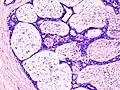

Macroscopic view of fibroadenoma of the breast

Macroscopic

Approximately 90% of fibroadenomas are less than 3 cm in diameter. However, these tumors have the potential to grow reaching a remarkable size, particularly in young individuals. The tumor is round or ovoid, elastic, and nodular, and has a smooth surface. The cut surface usually appears homogenous and firm, and is grey-white or tan in colour. The pericanalicular type (hard) has a whorly appearance with a complete capsule, while the intracanalicular type (soft) has an incomplete capsule.[9]

Fibroadenoma of the breast is a benign tumor composed of a biplastic proliferation of both stromal and epithelial components.[12][13] This biplasia can be arranged in two growth patterns: pericanalicular (stromal proliferation around epithelial structures) and intracanalicular (stromal proliferation compressing the epithelial structures into slit-like spaces).

These tumors characteristically display hypovascular stroma compared to malignant neoplasms.[2][14][9] Furthermore, the epithelial proliferation appears in a single terminal ductal unit and describes duct-like spaces surrounded by a fibroblastic stroma. The basement membrane is intact.[15]